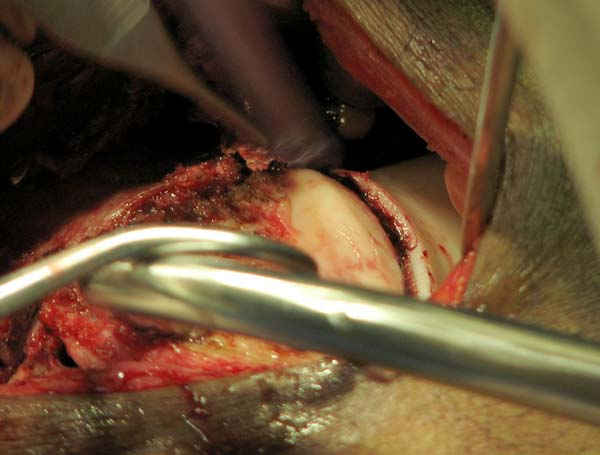

Позвольте привести пример из собственной московской практики в поддержку тактики, приведенной в данном примере. Пациент переведен из одной из московских клиник на 3 сутки после сквозного огнестрельного ранения плеча(пистолет)с ушитыми узловыми швами и дренированными резиновым выпускником ранами на внутренней поверхности плеча с умеренным серозногнойным отделяемым и похожей раной на задненаружной поверхности грудной клетки (пуля прошла через плечо и остановилась в мышцах спины). Также имелись реактивный локтевой бурсит и нейропатия локтевого нерва. При поступлении были сняты швы, начата антибиотикотерапия. Через сутки после травмы пациент прооперирован: выполнена повторная хирургическая обработка ран плеча и грудной клетки. Через отдельные доступы на наружной поверхности плеча произведен минимально инвазивный остеосинтез плечевой кости блокируемой метадиафизарной пластиной. Пациент выписан на 4 сутки после операции. Дальнейшее течение гладкое, все раны зажили первичным натяжением. Еще раз пациент был госпитализирован через 4 месяца после операции с переломом этого же плеча на границе средней и дистальной третей: коллеги по криминальному ремеслу применили к нему слишком жесткие меры убеждения. Выполнен остеосинтез путем замены и добавления винтов в дистальной части пластины. Госпитализация 2 суток. К сожалению, последние снимки не сохранились.